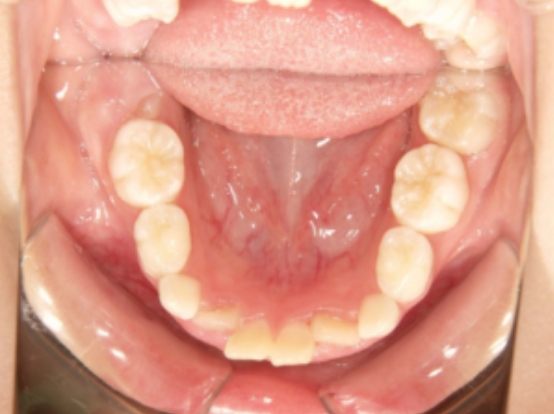

9y7m:ベロ機能の練習前

上の歯列弓の中に納まらない状態